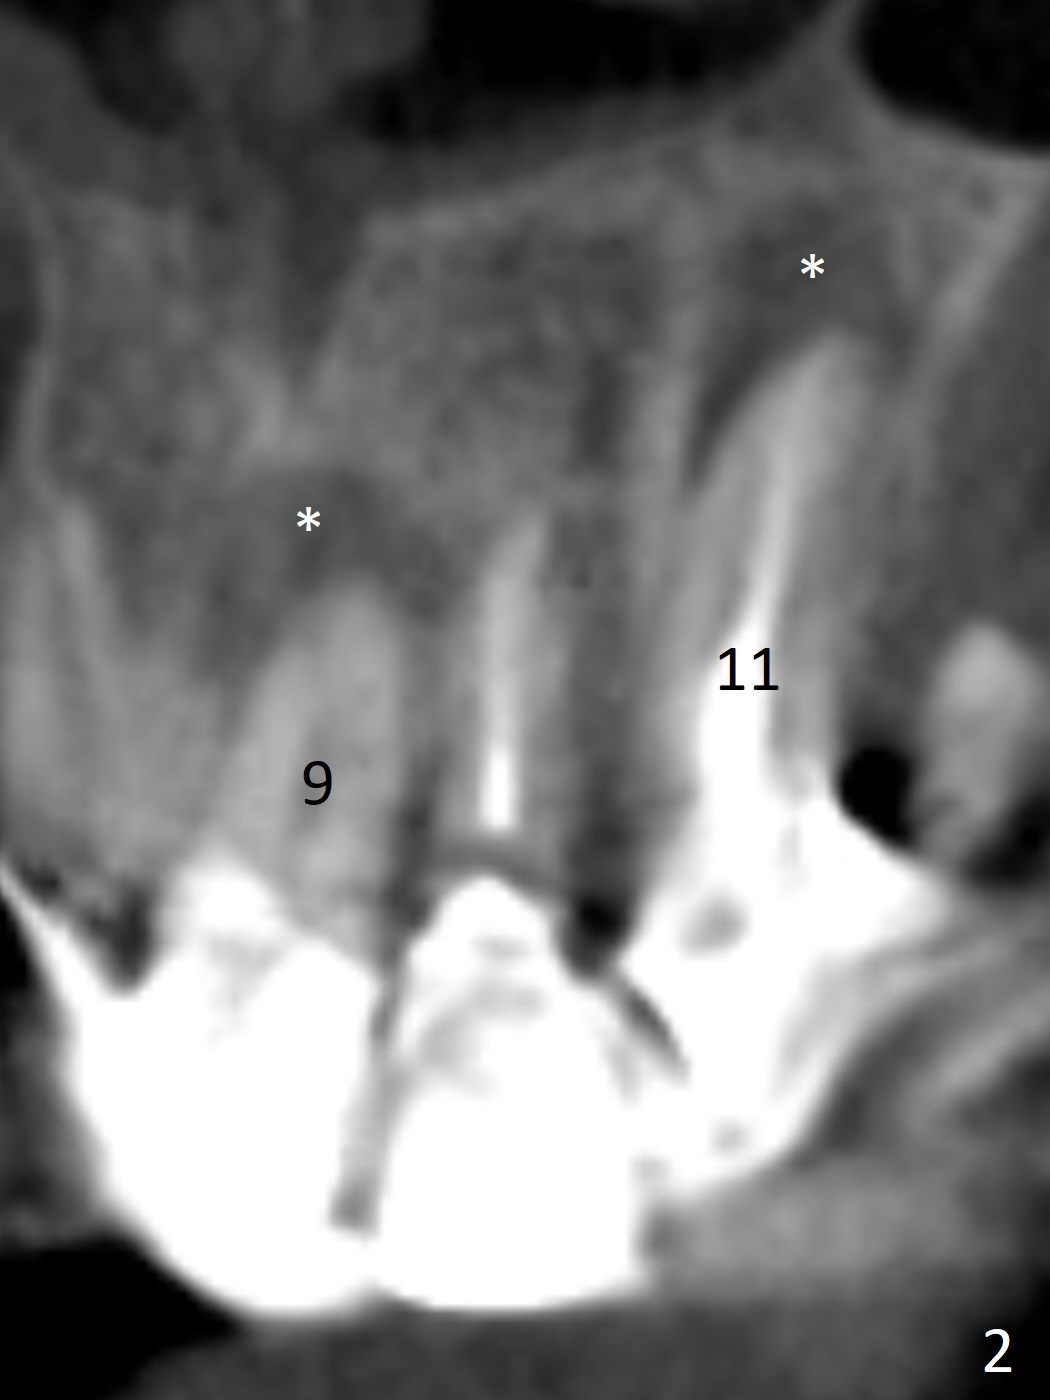

A 60-year-old man fractures the tooth #10 after implant at #7 (Fig.1). An implant should be placed in the middle of the socket at #10 since there is periapical radiolucencey at #9 and 11 (Fig.2 CBCT). The buccal plate at #10 is thin (Fig.4). A 3.8x15 mm implant (the smallest 2-piece) appears to be large for the alveolus (Fig.5). The gingiva must be thin as well. This is called thin biotype. In fact the buccal plate seems to have undergone bone resorption post 3.8x15 mm implant placement at #7. Therefore a 2.5 or 3x14 or 16 mm 1-piece implant will be placed at #10 (Fig.5). Also prepare angled ones. Take photos of #7 and 10 to show bone resorption and the thin gingiva. If the caries is not extensive, perform socket shield. In fact a 1-piece implant is chosen because of the narrow mesiodistal space.